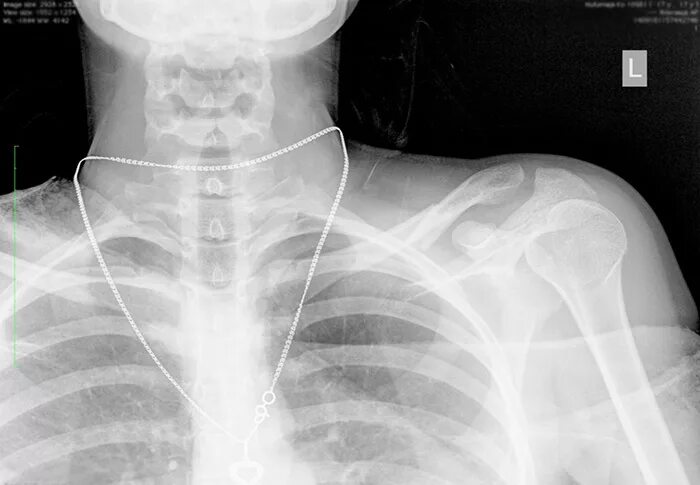

Хрустит ключица